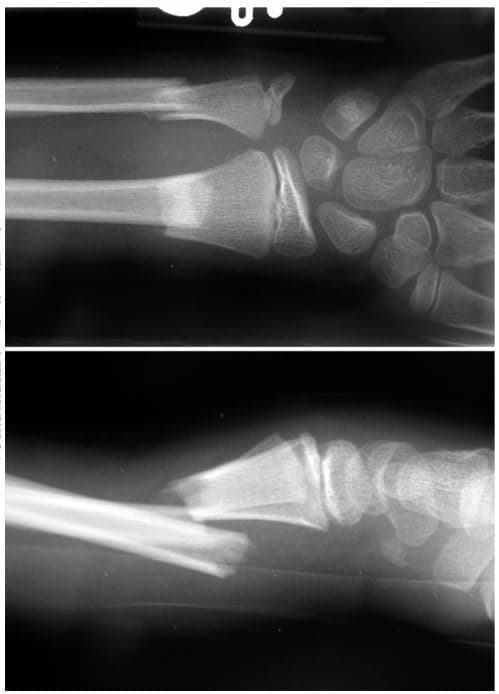

How would you describe the fracture?

Name the type of fracture

List ALL the bones present

What may have caused this abnormality?